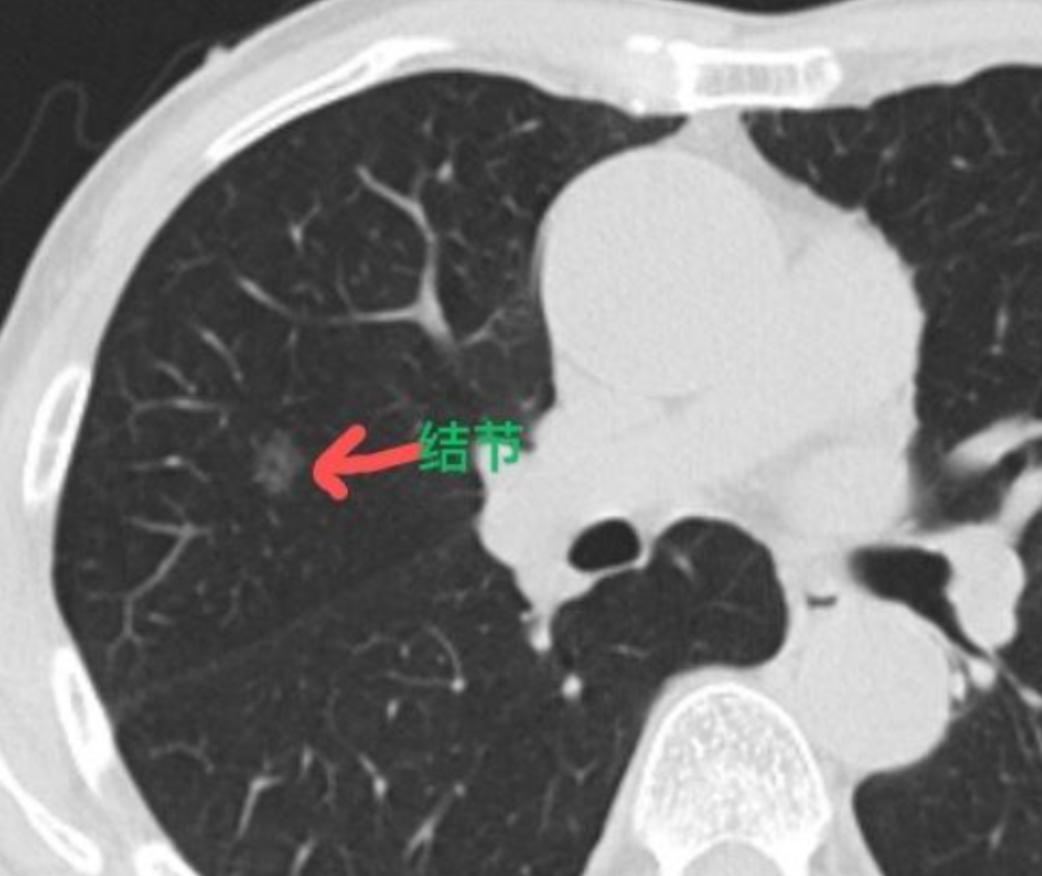

一男子十年前做了右肾摘除术,近日偶感不适去医院检查,却发现检查报告上显示:左右肾完好无损。问题出在哪里呀,难道这兄弟又长出了右肾? 陈刚拿着这份报告,手指都攥得发白,脑子里嗡嗡响。十年前那场车祸的疼还像在昨天——当时他浑身是血被抬进手术室,医生出来跟家属说“右肾碎成渣了,必须摘,不然命保不住”。这十年他活得比谁都小心:不敢熬夜,不敢喝大酒,连搬个矿泉水桶都得找人帮忙,就怕剩下的左肾扛不住。每次体检报告上“左肾正常,右肾缺如”那行字,他都能背下来了,怎么今天突然冒出来两个肾? 他揣着报告一路小跑冲到医生办公室,把纸往桌上一摊:“大夫你瞅瞅!这不对啊!我右肾早没了,这报告是不是印错了?”坐诊的王医生推了推眼镜,先核对了报告上的照片和姓名——是陈刚没错,再翻他带来的旧病历,2013年的手术记录清清楚楚写着“右肾全摘除术”。王医生也懵了:“这事儿邪门儿了,我给你开个B超复查单,再仔细扫一遍,总不能真长出来了吧?” 陈刚捏着复查单,心里七上八下的。路上还琢磨:难道是医学奇迹?可电视上也没见过肾能再生啊,别是长了什么瘤子被当成肾了?到了B超室,医生涂耦合剂的时候问:“以前做过肾手术?”陈刚点头:“右肾摘了十年了。”医生盯着屏幕看了半天,皱着眉说:“右边这儿有个回声区,但形状跟正常肾不一样……等结果出来让主治医生看看吧。” 半小时后,复查结果出来了。王医生拿着新的B超图和陈刚十年前的手术记录对比了五分钟,突然拍了下桌子:“哦!找到了!你看这报告上的检查编号——昨天下午有个叫陈钢(钢铁的钢)的病人,跟你同名不同字,他的B超结果被护士误传到你这儿了!那小子没做过手术,所以双肾正常!你自己的复查结果是左肾功能良好,右边就是术后的瘢痕组织,啥事儿没有!” 陈刚听完,腿都软了,扶着墙长出一口气:“我的娘啊,吓死我了!我还以为自己得了啥怪病要完蛋了呢!”王医生也笑着道歉:“是我们科室的疏忽,给你添堵了。你这次的不适就是最近加班太累,左肾有点轻微劳损,回家歇几天,别吃太咸的就行。” 陈刚拿着正确的报告走出医院,太阳晒在脸上暖乎乎的。虽然虚惊一场,但也算是个教训——以后拿到报告得先看清楚编号和细节,医院也得更仔细点,不然这心脏真经不起这么折腾。他摸了摸肚子,心里念叨:得亏只是搞错了,要是真有啥事儿,这十年的小心谨慎不白搭了?回家赶紧炖个汤补补,以后可不敢再熬夜了。 (字数:823)